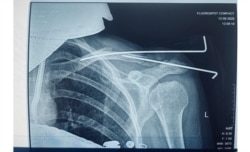

Як высьветлілася, куля пацэліла мне ў плячо, разьбіўшы ключыцу на аскепкі. Уласьцівасьць гумавых куль — пранікаюць неглыбока, але ствараюць магутную ўдарную хвалю. Таму страляць гумавымі кулямі ў корпус і ў галаву ні ў якім разе нельга.

У мяне атрымалася кантузія на палову тулава (варта было крыху напружыць цягліцы — і адразу быў боль да самага чэрапа), гематома на сьпіне, якая і празь месяц да канца не сышла, і адкрыты пералом з ранай больш за 10 см у даўжыню і некалькі сантымэтраў у шырыню. Мне ў плячо кожны дзень закладвалі па два тампоны, каб хоць неяк спыняць кроў.

І зноў: некалькі дзён ляжаць у лужыне ўласнай крыві — гэта цяпер шанцунак. Калі на першай апэрацыі мяне ўводзілі ў наркоз, дактары абмяркоўвалі, ці варта захоўваць нагу 16-гадоваму хлопцу ў штучнай коме, або ён мае больш шанцаў выжыць з ампутацыяй. У часе другой апэрацыі, ужо пад мясцовай анэстэзіяй, я тры гадзіны слухала, як дактары пілуюць маю ключыцу. Як у іх не атрымліваецца і робяць наноў. Як пальцамі перабіраюць цягліцы і ўстаўляюць жалезныя сьпіцы ў абломкі косткі. Як крэсла пада мной развальваецца ад старасьці, а лямпа падае на галаву. У другім канцы апэрацыйнай хірург гучна абураўся: «Вось прыдуркі, яйцы ім паадрываць. Яны па мітынгах ходзяць, а я ім чацьвёрты дзень кулі з азадкаў дастаю!»

Дактары не казалі, што ў мяне пералом, да наступнага дня. Празь дзень сказалі, што адкрыты пералом. Яшчэ празь дзень, што будуць мне зьбіраць ключыцу. Як мне сказалі, паводле ваенна-палявой хірургіі маё раненьне ацэньваецца як ня вельмі складанае. Нягледзячы на тое, што было тры апэрацыі на плячы і ўскладненьне на лёгкае.

Другі месяц я на бальнічным. Днямі мне выцягваюць сьпіцы… Два аскепкі косткі зрасьліся даволі роўна, адзін крыху выпірае — я ўжо цяпер магу адчуць невялікую выпукліну. Вядома, усё гэта баліць і цягне кожны дзень, але не кругласутачна і па-рознаму.

Часам, калі пераварочваюся, чую, як шчоўкае нешта. Гэта трохі жудасна. Але да гэтага прывыкаеш. Левая рука нашмат танчэйшая за правую — цягліцы атрафаваліся. І ёсьць цягучы боль уздоўж цягліц. Я думаю, гэта ўсё вернецца, калі здымуць павязку і я буду распрацоўваць руку. Дактары кажуць, колькі была зьнерухомленая рука, прыкладна столькі ж функцыі будуць аднаўляцца. Зрэшты, я цяпер адной рукой толькі коўдру ў чахол не запраўлю, а так усё магу. І працую адной рукой — не хачу падстаўляць калег.

У пэрспэктыве будзе прыгожы шнар на ўсё плячо. Я ня буду лазэрам зводзіць яго. Я гэта не хачу забываць.